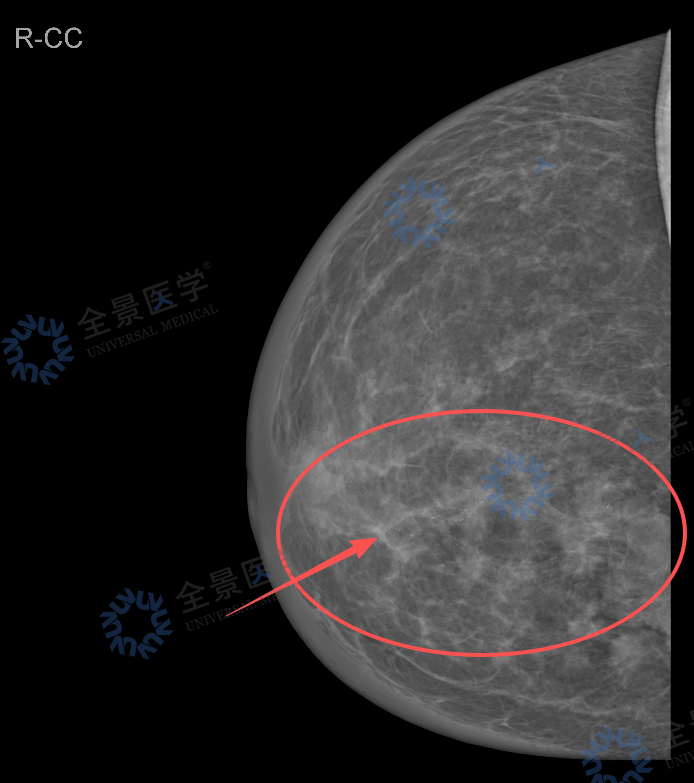

· 钼靶提示右乳多发高密度影伴钙化,BI-RADS 4B~4C;

钼靶: 利用低能 X 线穿透乳腺软组织,靠组织密度差异成像。对 40 岁以上女性友好,擅长发现微小钙化,是早期乳腺癌筛查的「金标准」。